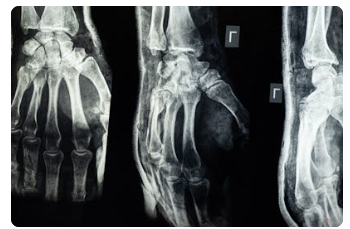

오늘은 '소리 없는 뼈 도둑'이라 불리는 골다공증에 대해 깊이 알아보겠습니다. 골다공증은 뼈의 양이 감소하고 질이 변하여 뼈가 약해지고 부러지기 쉬운 상태를 말합니다. 특히 노년기 삶의 질을 크게 떨어뜨릴 수 있는 질환이므로 미리 알고 대비하는 것이 중요합니다. 이 글을 통해 골다공증의 주요 원인부터 최신 경향, 효과적인 치료법과 진료과, 그리고 가장 중요한 예방법까지 상세히 알려드리겠습니다.

골다공증은 조기에 발견하고 꾸준히 관리하면 충분히 건강한 뼈를 유지하고 골절 위험을 낮출 수 있는 질환입니다. 정기적인 골밀도 검사를 통해 자신의 뼈 상태를 확인하고, 오늘 알려드린 건강한 생활 습관을 꾸준히 실천하여 '뼈 건강'을 지키시길 바랍니다.